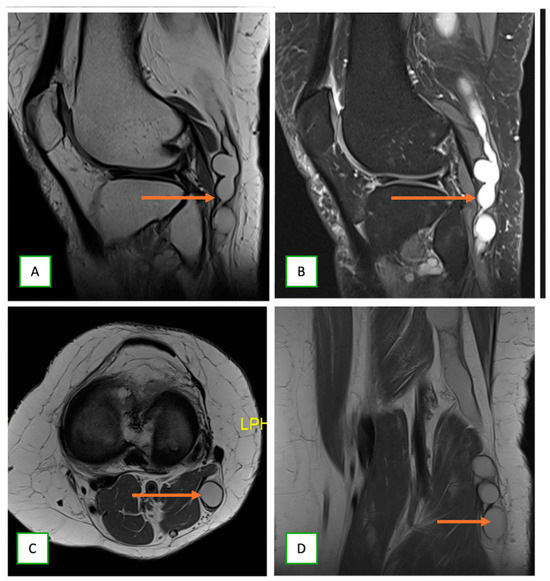

- Intraneural ganglion cysts usually occur near joints; are particularly common in the common peroneal nerve at the knee, owing to the intraarticular branch of the proximal tibiofibular joint; and appear as tubular, multiloculated cystic lesions following the course of the nerve on MRI [60,61] (Figure 16).